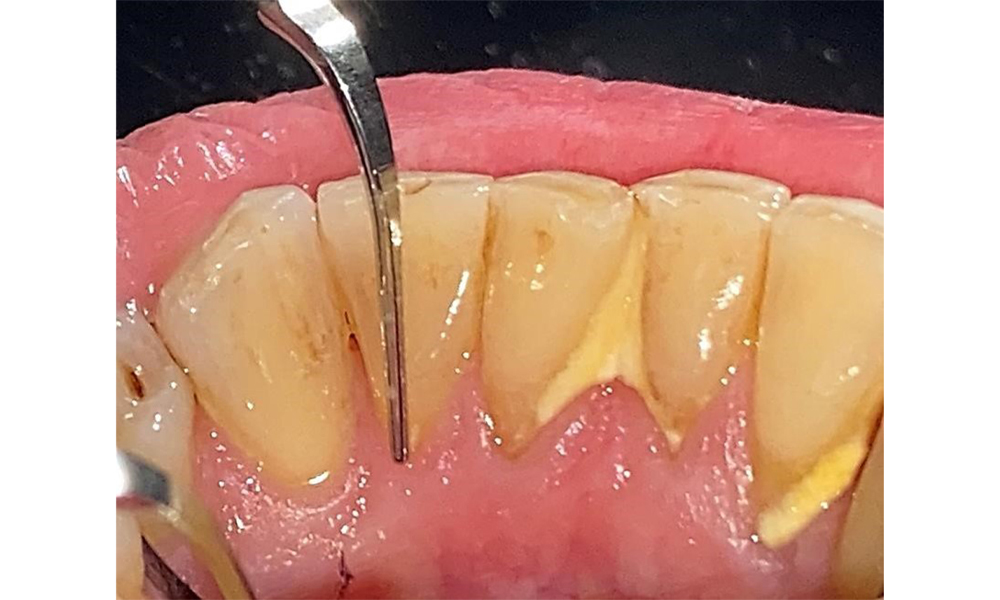

The documentation of periodontal findings, including pocket depth probing and bleeding status, is mandatory during each dental appointment due to the presence of periodontitis (Fig. 8). This will record the individual therapeutic needs and facilitate a rapid response to any progression of the pre-existing periodontitis.

There are no limitations regarding the choice of instrumentation methods. Regular supragingival and subgingival instrumentation is essential to prevent disease progression due to the pre-existing periodontitis and high risk of recurrence. There are no limitations placed on the selection of instruments for mechanical biofilm removal from a general medical perspective, and removal should be performed as needed. Hard and mineralized plaque, such as calculus and concretions, should be removed using manual instruments or sonic/ultrasonic scalers (Fig. 9) (8, 9).